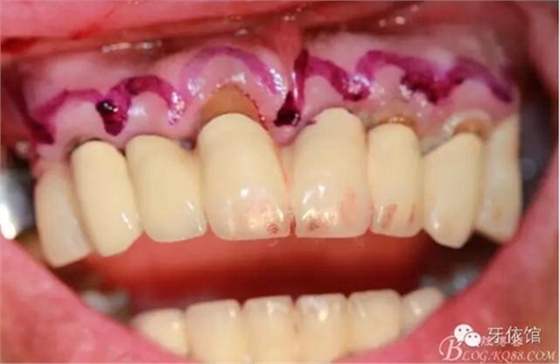

術(shù)中口內(nèi)照

降低骨高度,左右1,2骨寬度嚴(yán)重不足,決定將前牙2——2區(qū)間植體植在切牙孔內(nèi)